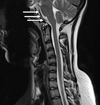

11

Q

A

C3/4 facet joint